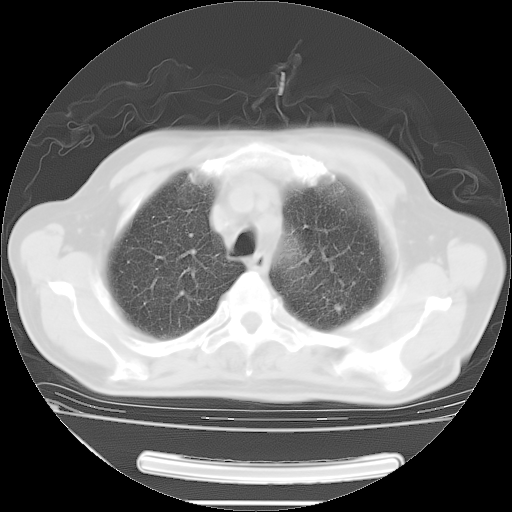

今天复查肺部CT,发现双肺广泛磨玻璃样改变。所以我把3月19日和5月9日相隔50天的肺部CT上传。请大家会诊。

2009年3月19日肺部CT片。

2009年3月19日肺部CT

5月9日肺部CT(在4月27日齐鲁医院肺部CT描述部分肺组织磨玻璃样改变,12天后肺组织广泛磨玻璃样改变)

大致读了系列胸部CT:纵隔窗无明显异常,肺窗:从4、27至今:主要是双肺中下野外带可见毛玻璃样改变,目前处于急性肺泡炎阶段,至于原因考虑1、结替组织或胶原血管性疾病所致?2、恶性疾病如恶组在肺部所致的表现或细支气管肺泡癌?3、药物或其它原因如肺蛋白沉着症所致肺泡炎目前不太可能?总之,明天就去请我院的呼吸科、感染科、血液科和临免专家会诊哈。